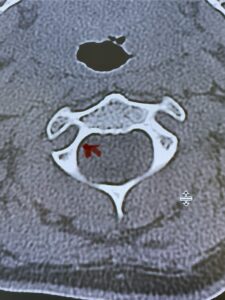

Cervical x-rays revealed a significantly increased atlanto-axial interval (Fig. 5) On review of her imaging studies it was noted that the right C2 isthmus was very thinned by the vertebral foramen (Figs 6a, b, and c) which would make an attempt at placing a C2 pars screw dangerous. A decision was made to perform an occipital-cervical fusion because only possible unilateral fixation and an extensive C1 laminectomy to be performed eliminating a fixation point if a more traditional C1-C2 was performed. Even if C1 lateral mass screws were able to be placed one could only perform a unilateral screw construct fixation to C2. We performed an occipital cervical fusion down to C4 to get enough inferior fixation and C1 laminectomy. The decompression went well. We placed a left unilateral pars screw and bilateral C3 and C4 lateral mass screws. We placed three 12 mm screws in the midline keel (Fig. 7). Postoperatively the patient had all around improvement in her symptoms and did not qualify for rehab. Her post op films at 6 weeks (Fig. 8)

Fig. 6c: Axial cervical CT scan demonstrating a very thin right C2 isthmus (red arrow) compared to left side.